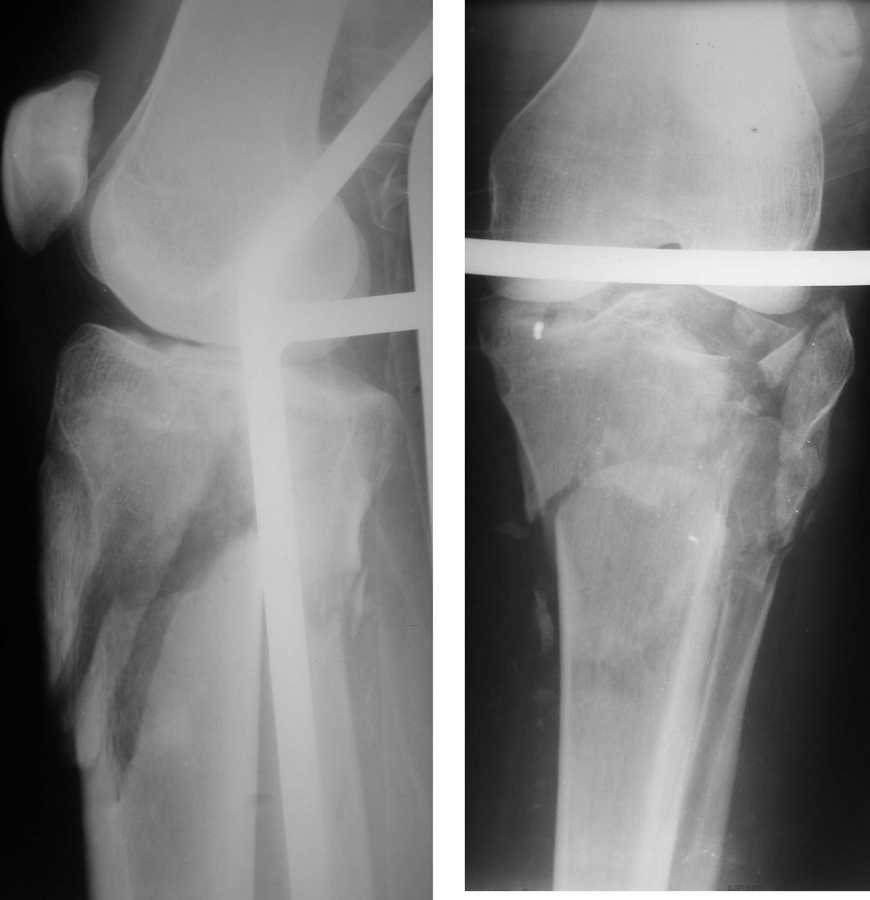

Приветствую всех.Вот такой перелом - неделю назад. Лет 25.

Открытый раздробленный перелом проксимального отдела большеберцовой кости. Имеется рана, ушитая, и заживающие фликтены (со слов родственников). Скелетное вытяжение.

Саша, а в чем конкретно неясность? Надо полагать, вопрос не про общие принципы лечения переломов типа Schatzker VI или C3 по классификации AO, которые можно найти в любом руководстве?